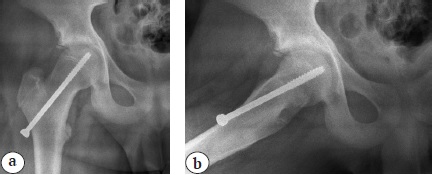

Техника операции

Все дети получили хирургическое лечение, заключающееся в фиксации проксимальных эпифизов обеих бедренных костей с использованием электронно-оптического преобразователя (ЭОП) рентгеновского изображения. Для фиксации применялись самонарезающие канюлированные винты диаметром 7,0 мм с наружной резьбовой нарезкой на конце, занимающей около одной четверти общей длины. Винт вводился в эпифиз с передненаружной поверхности бедренной кости через шейку и центр ростковой пластинки, при этом головка винта не опиралась на кортикальный слой, а отстояла от бедренной кости на 5–10 мм (рис. 1).

Рис. 1. Рентгенограммы правого тазобедренного сустава в переднезадней проекции (а) и в проекции Лауэнштейна (b) пациента 13 лет 11 мес. непосредственно после операции. Объяснение в тексте